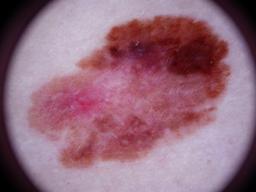

{

"age_approx": 55,

"anatom_site_general": "head/neck",

"concomitant_biopsy": true,

"diagnosis_1": "Malignant",

"diagnosis_2": "Malignant melanocytic proliferations (Melanoma)",

"diagnosis_3": "Melanoma, NOS",

"diagnosis_confirm_type": "histopathology",

"image_type": "dermoscopic",

"lesion_id": "IL_7611472",

"melanocytic": true,

"sex": "male"

}